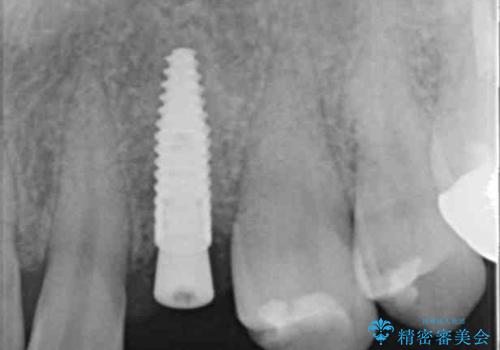

骨造成を伴う 前歯部インプラント治療

- 欠損している前歯のインプラント治療を希望され来院されました。

適切なインプラント埋入を行い、不足している骨量を補うため骨の造成を併用したインプラント治療を計画します。

前歯のインプラント治療は骨量・歯肉の厚み・インプラントの方向をしっかりと計画することで、審美的で長持ちを期待できるような仕上がりとなります。